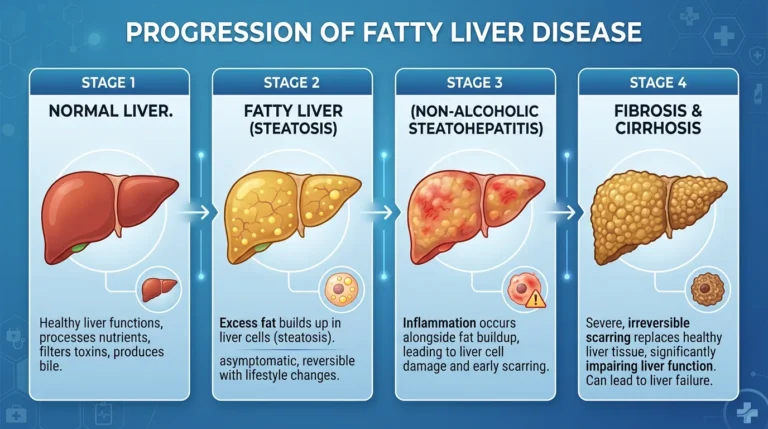

Stages of Fatty Liver Disease

Fatty liver progresses in different stages:

- Simple Fatty Liver – fat accumulation without inflammation

- NASH (Non-Alcoholic Steatohepatitis) – inflammation develops

- Fibrosis – liver tissue begins to scar

- Cirrhosis – severe and permanent liver damage

Early intervention can prevent progression to advanced stages.